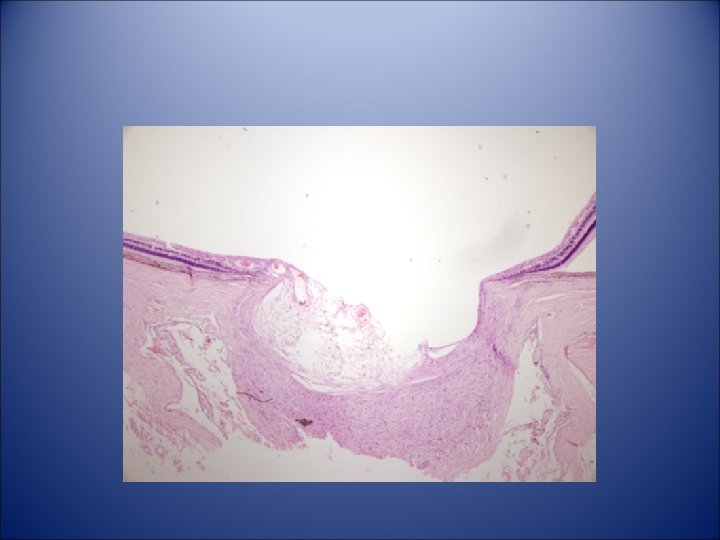

Diagnosis Malignant melanoma of anterior ciliary body and

• Diagnosis – Malignant melanoma of anterior ciliary body and iris root, spindle cell type with invasion of Schlemm’s canal and collector channels – Secondary glaucoma